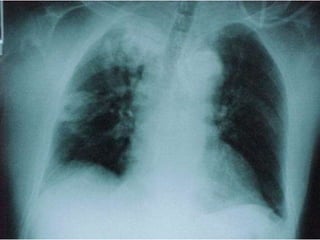

 Pulmonary disease: 70-75% isolates of

NTM

 Definition

 Usually adults

 Symptoms of cough, sputum production,

weight loss

 Two or more sputum isolates or one isolate

from, BAL, Bx, sterile site

 Distribution of isolates varies regionally

 MAC, rapid growers, M kansassi & M xenopi

 M.Kansasii

 Similar to TB

 US midwest and

south

 AFB positive

 Probe positive

 HIV CD4 <200

pulmonary and

disseminated

 X-RAY: chest, CAT thorax

 Pulmonary disease:70-75% isolates of NTM  Definition  Usually adults  Symptoms of cough, sputum production, weight loss  Two or more sputum isolates or one isolate from, BAL, Bx, sterile site  Distribution of isolates varies regionally  MAC, rapid growers, M kansassi & M xenopi

• 16.

 M.Kansasii  Similarto TB  US midwest and south  AFB positive  Probe positive  HIV CD4 <200 pulmonary and disseminated  M..xenopi  UK, Northern Europe and Canada, less common in US  Rural /farm area  Very good outcome